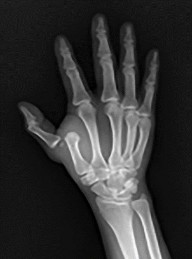

- العظام: يتكون المعصم من 8 عظام رسغية صغيرة، بالإضافة إلى عظمي الزند والكعبرة في الساعد. تتصل هذه العظام بخمسة عظام مشطية في اليد، والتي تتصل بدورها بعظام السلاميات في الأصابع والإبهام. كل إصبع يتكون من ثلاث سلاميات (قريبة ومتوسطة وبعيدة)، باستثناء الإبهام الذي يحتوي على سلاميتين فقط.

- المفاصل المشطية السلامية (MCP): تربط العظام المشطية بالسلاميات القريبة للأصابع.

- الأوتار: تربط العضلات بالعظام وتسمح بالحركة. لدينا أوتار قابضة تسمح بثني الأصابع والإبهام (مثل وتر العضلة المثنية العميقة للأصابع FDP ووتر العضلة المثنية الطويلة للإبهام FPL)، وأوتار باسطة تسمح بمد الأصابع والإبهام (مثل وتر العضلة الباسطة الطويلة للإبهام EPL).

- صعوبة في الإمساك بالأشياء (ضعف القبضة): شائع في العديد من حالات اليد والمعصم، بما في ذلك التهاب المفاصل، كسور الرسغ، وإصابات الأوتار.

- صعوبة في ثني الأصابع (خاصة السلامية البعيدة): قد يشير إلى تمزق وتر العضلة المثنية العميقة للأصابع (FDP).

- صعوبة في مد الإبهام: قد يدل على تمزق وتر العضلة الباسطة الطويلة للإبهام (EPL).